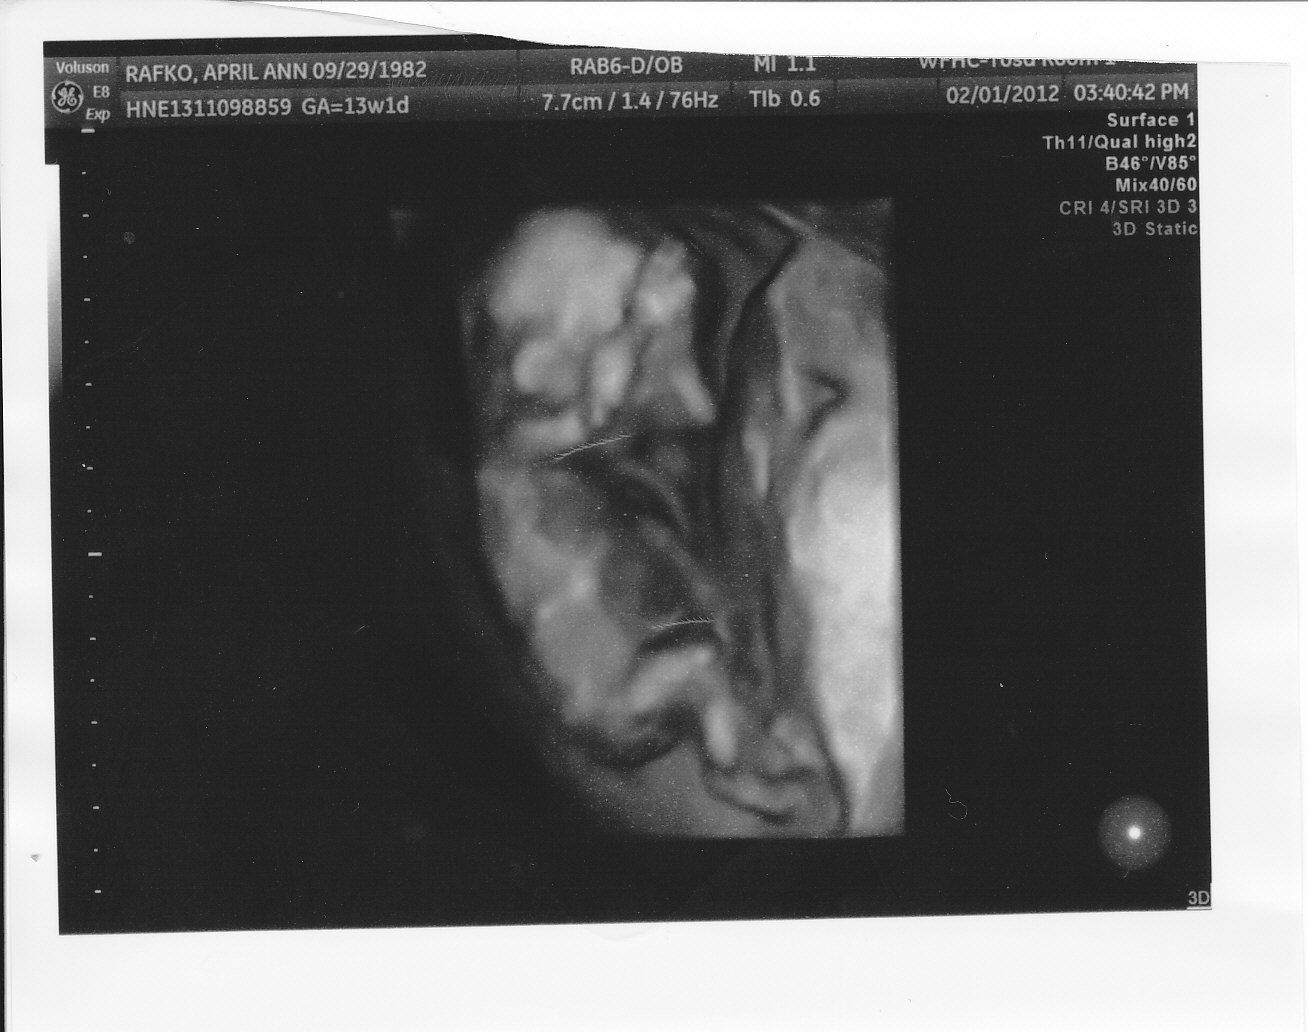

Here are two more photos from the same u/s...do either of these help?

I *thought* in the first pic it could go either way, but the 2nd pic looks girlie to me, so I'm guessing girl. Good luck.

Now I think maybe girl LOL!

So according to the skull theory does this look like a boy or girl? I was trying to figure it out but I'm really new. In some I really thought girl because it seems rounded. Am looking at it correctly?

I think the skull looks girly. GL!!!